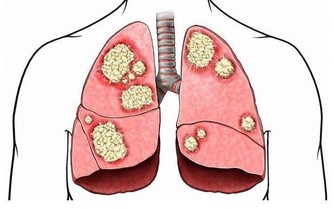

4、多吃黃色蔬菜、紅薯、南瓜、西紅柿和胡蘿蔔等新鮮綠色蔬菜,內含豐富的胡蘿蔔素,

對兒童及成人均有重要的提高免疫力、減少感染、減低腫瘤發病機會的作用。